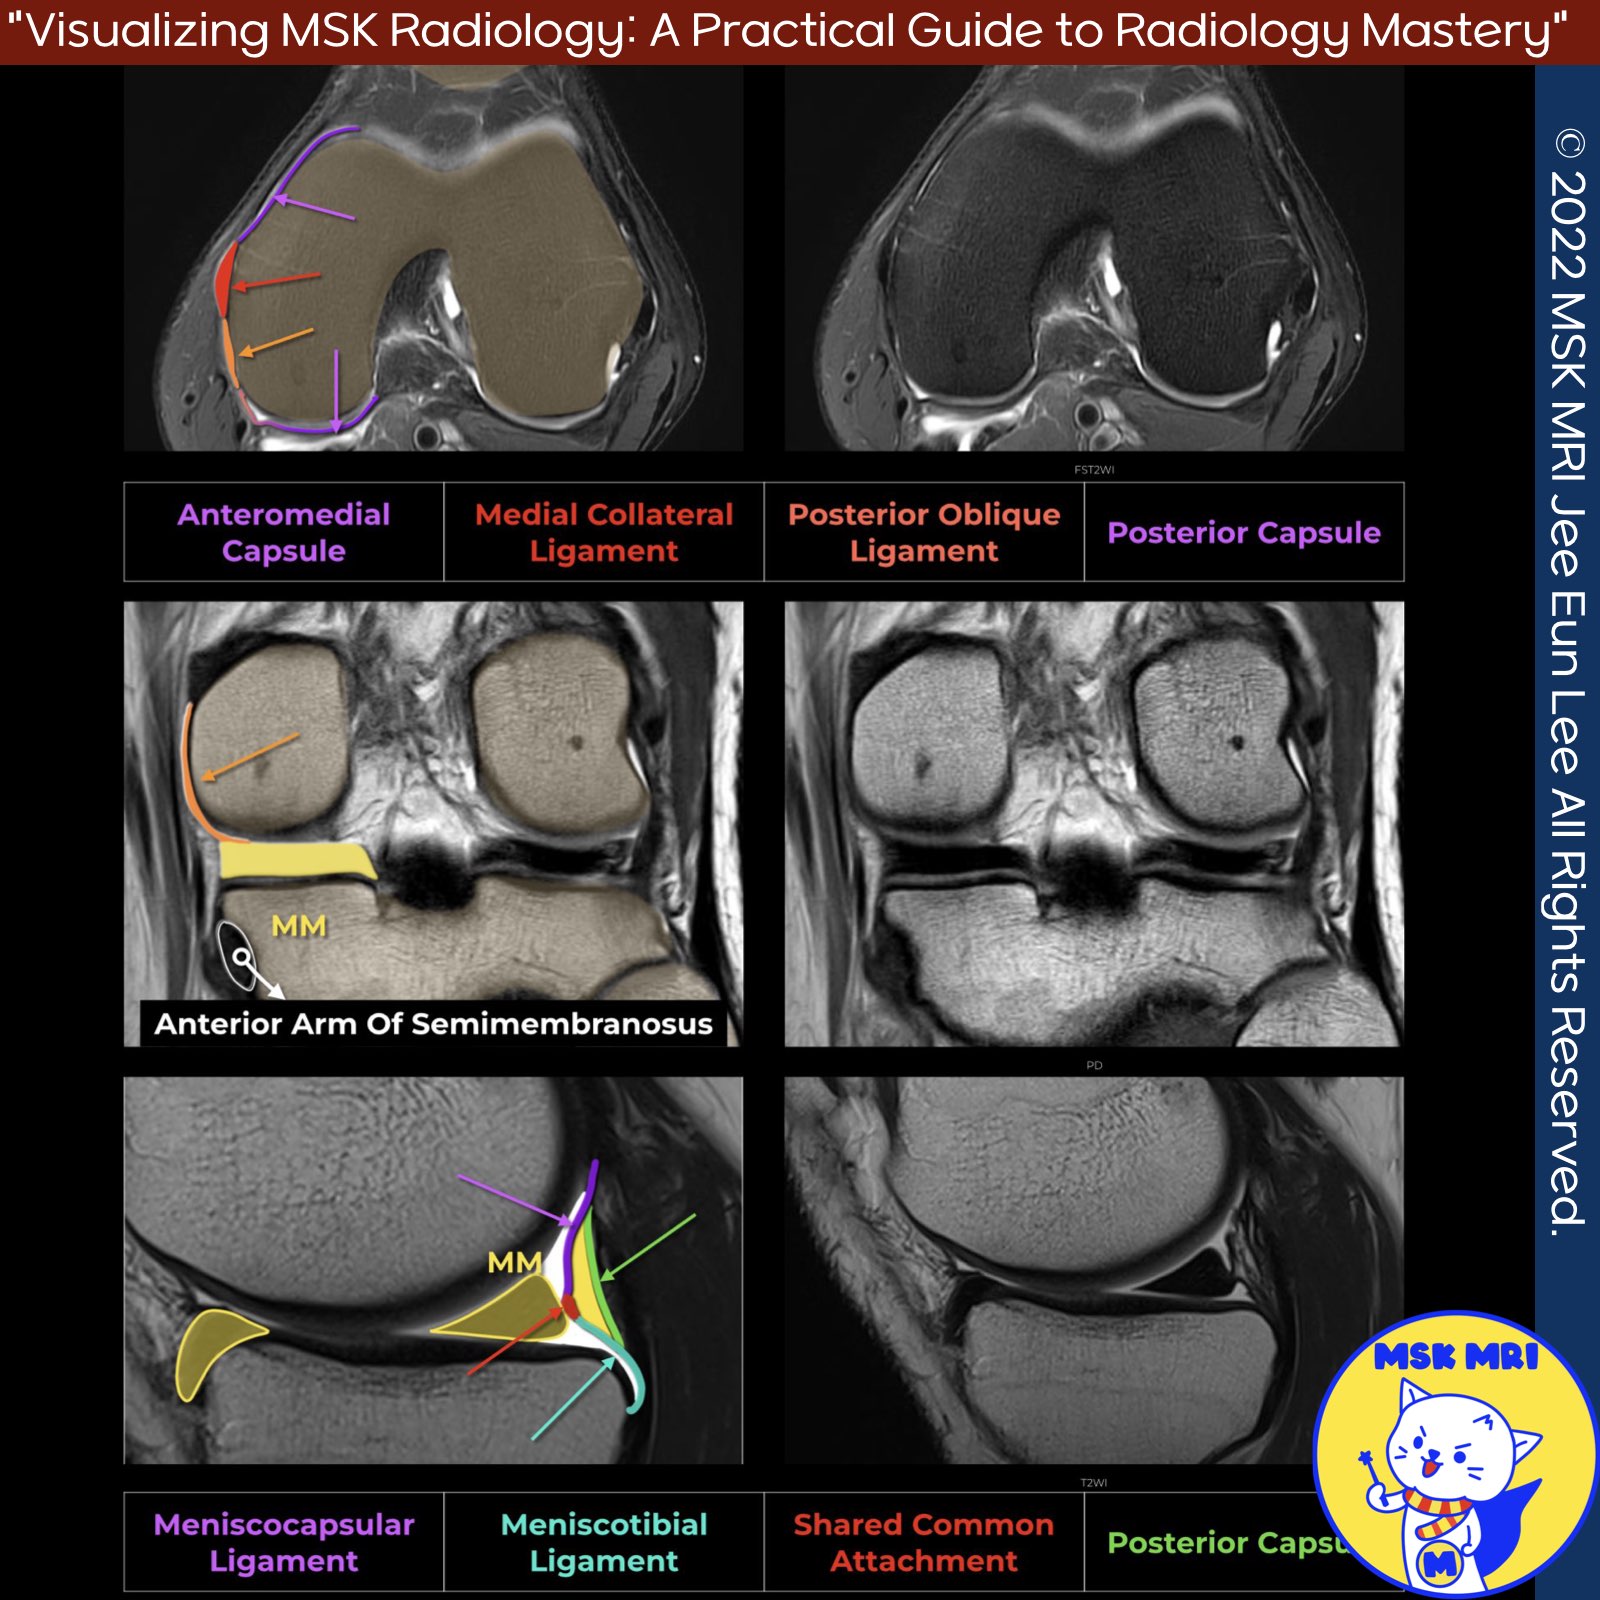

📌 MRI Anatomy of the Posterior Oblique Ligament

✅ Proximal Attachments

The posterior oblique ligament (POL) originates near the adductor tubercle from the posterior margin of the superficial medial collateral ligament (sMCL), where the sMCL fuses with the deep medial collateral ligament.

Visualization The POL is best visualized on coronal and axial MRI sequences. Proximally, it can be identified immediately posterior to the sMCL. However, more distally it becomes difficult to separate from the posteromedial capsule.

✅ Distal Attachments

The main distal attachments of the POL include:

- Tibia

- Posterior horn of the medial meniscus

- Sheath of the semimembranosus tendon

- Posteromedial joint capsule

✅ Three main arms or components:

- Capsular arm - Blends with posteromedial capsule

- Central arm - Inserts into medial meniscus and adjacent tibia

- Superficial arm - Extends superficial to semimembranosus tendon